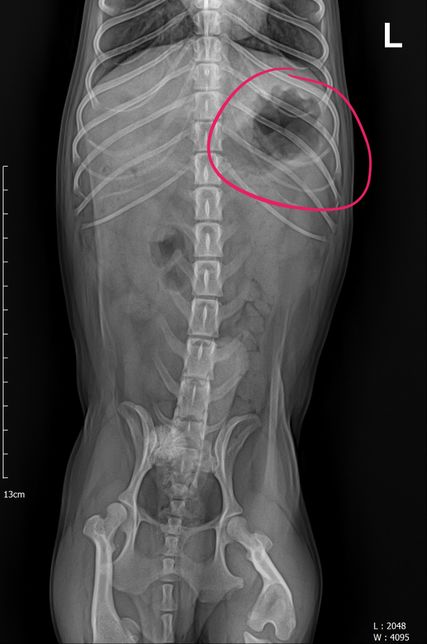

- 반려동물 건강반려동물Q. 강아지 엑스레이 한 번만 더 봐주세요 부탁드립니다어제 유선종양 한 토이푸들 견주입니다. 어제 수술 전 찍은 엑스레이인데 혹시 저 동그라미 친 곳이 유선종양일까요? 종양이 아니라면 뭘까요..? 그리고 엑스레이 상으로 전이소견은 안 보이는 거 맞죠..? 따로 또 문제 되보이는게 있을까요?그리고 종양이 여러개인데 한 개만 조직검사를 의뢰했어요 양성의 결과가 나와도 여러개의 종양 중 한 개만 조직검사를 의뢰했던 거니까 추적관찰은 해주는게 좋은가요..?